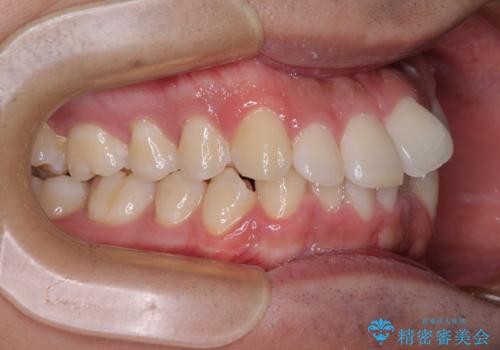

- 前歯のデコボコを治したいとのことで来院された患者様です。

上下顎ともに歯列全体の後方移動とIPR(歯と歯の間を削る)によってデコボコが解消するように設計し、インビザラインにより治療を行うこととしました。

下顎前歯は後戻りを起こしやすいため、舌側を細いワイヤーで固定し、マウスピース型リテーナーで保定を行うこととしました。